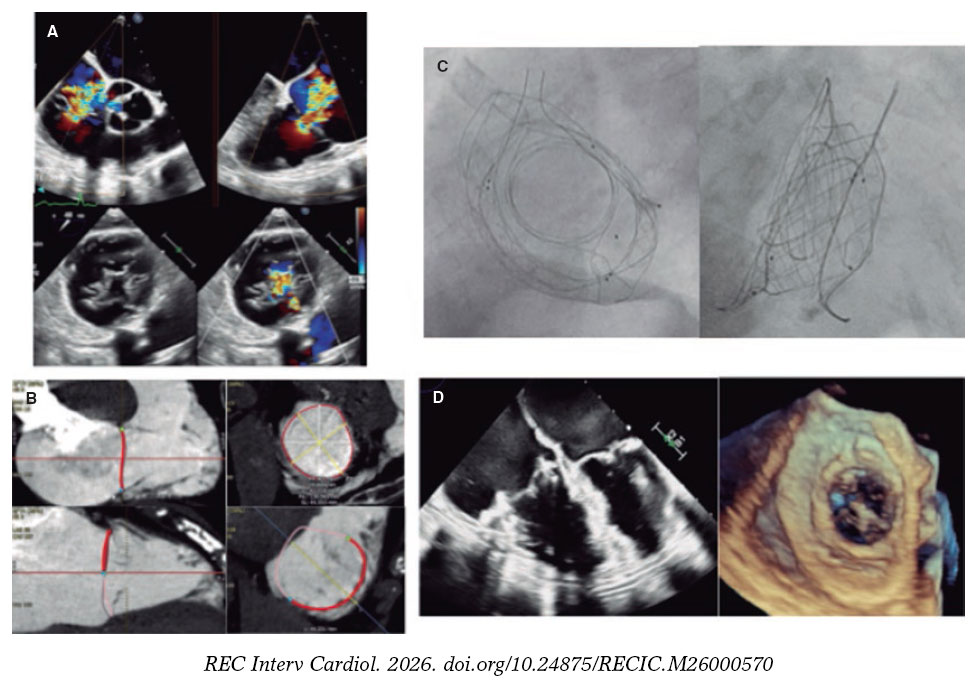

El reemplazo de válvula tricúspide percutáneo (RVTP) constituye una alternativa emergente para pacientes de alto riesgo quirúrgico con insuficiencia tricuspídea aislada, grave y sintomática, en especial cuando la anatomía no permite la reparación percutánea. Se presenta el primer caso en España de RVTP con la nueva prótesis percutánea VDyne Valve (VDyne, Estados Unidos), diseñada para preservar la morfología asimétrica del anillo tricuspídeo. La prótesis, de nitinol y doble marco, alberga una válvula porcina trivalva de 30 mm. El marco externo asimétrico se adapta a anillos de 42-56 mm y se fija mediante anclaje en el tracto de salida del ventrículo derecho (TSVD), con pestañas en la pared libre, una lengüeta posteroseptal y una cola ventricular (figura 1). El dispositivo se monta verticalmente en un sistema de liberación femoral de 32 Fr. Sus ventajas con respecto a otros sistemas de RVTP incluyen el anclaje independiente de la visualización y el soporte de los velos nativos, la mínima interacción con el ápex y la posibilidad de recaptura total y de reposicionamiento tras la apertura intracardiaca.

Figura 1.